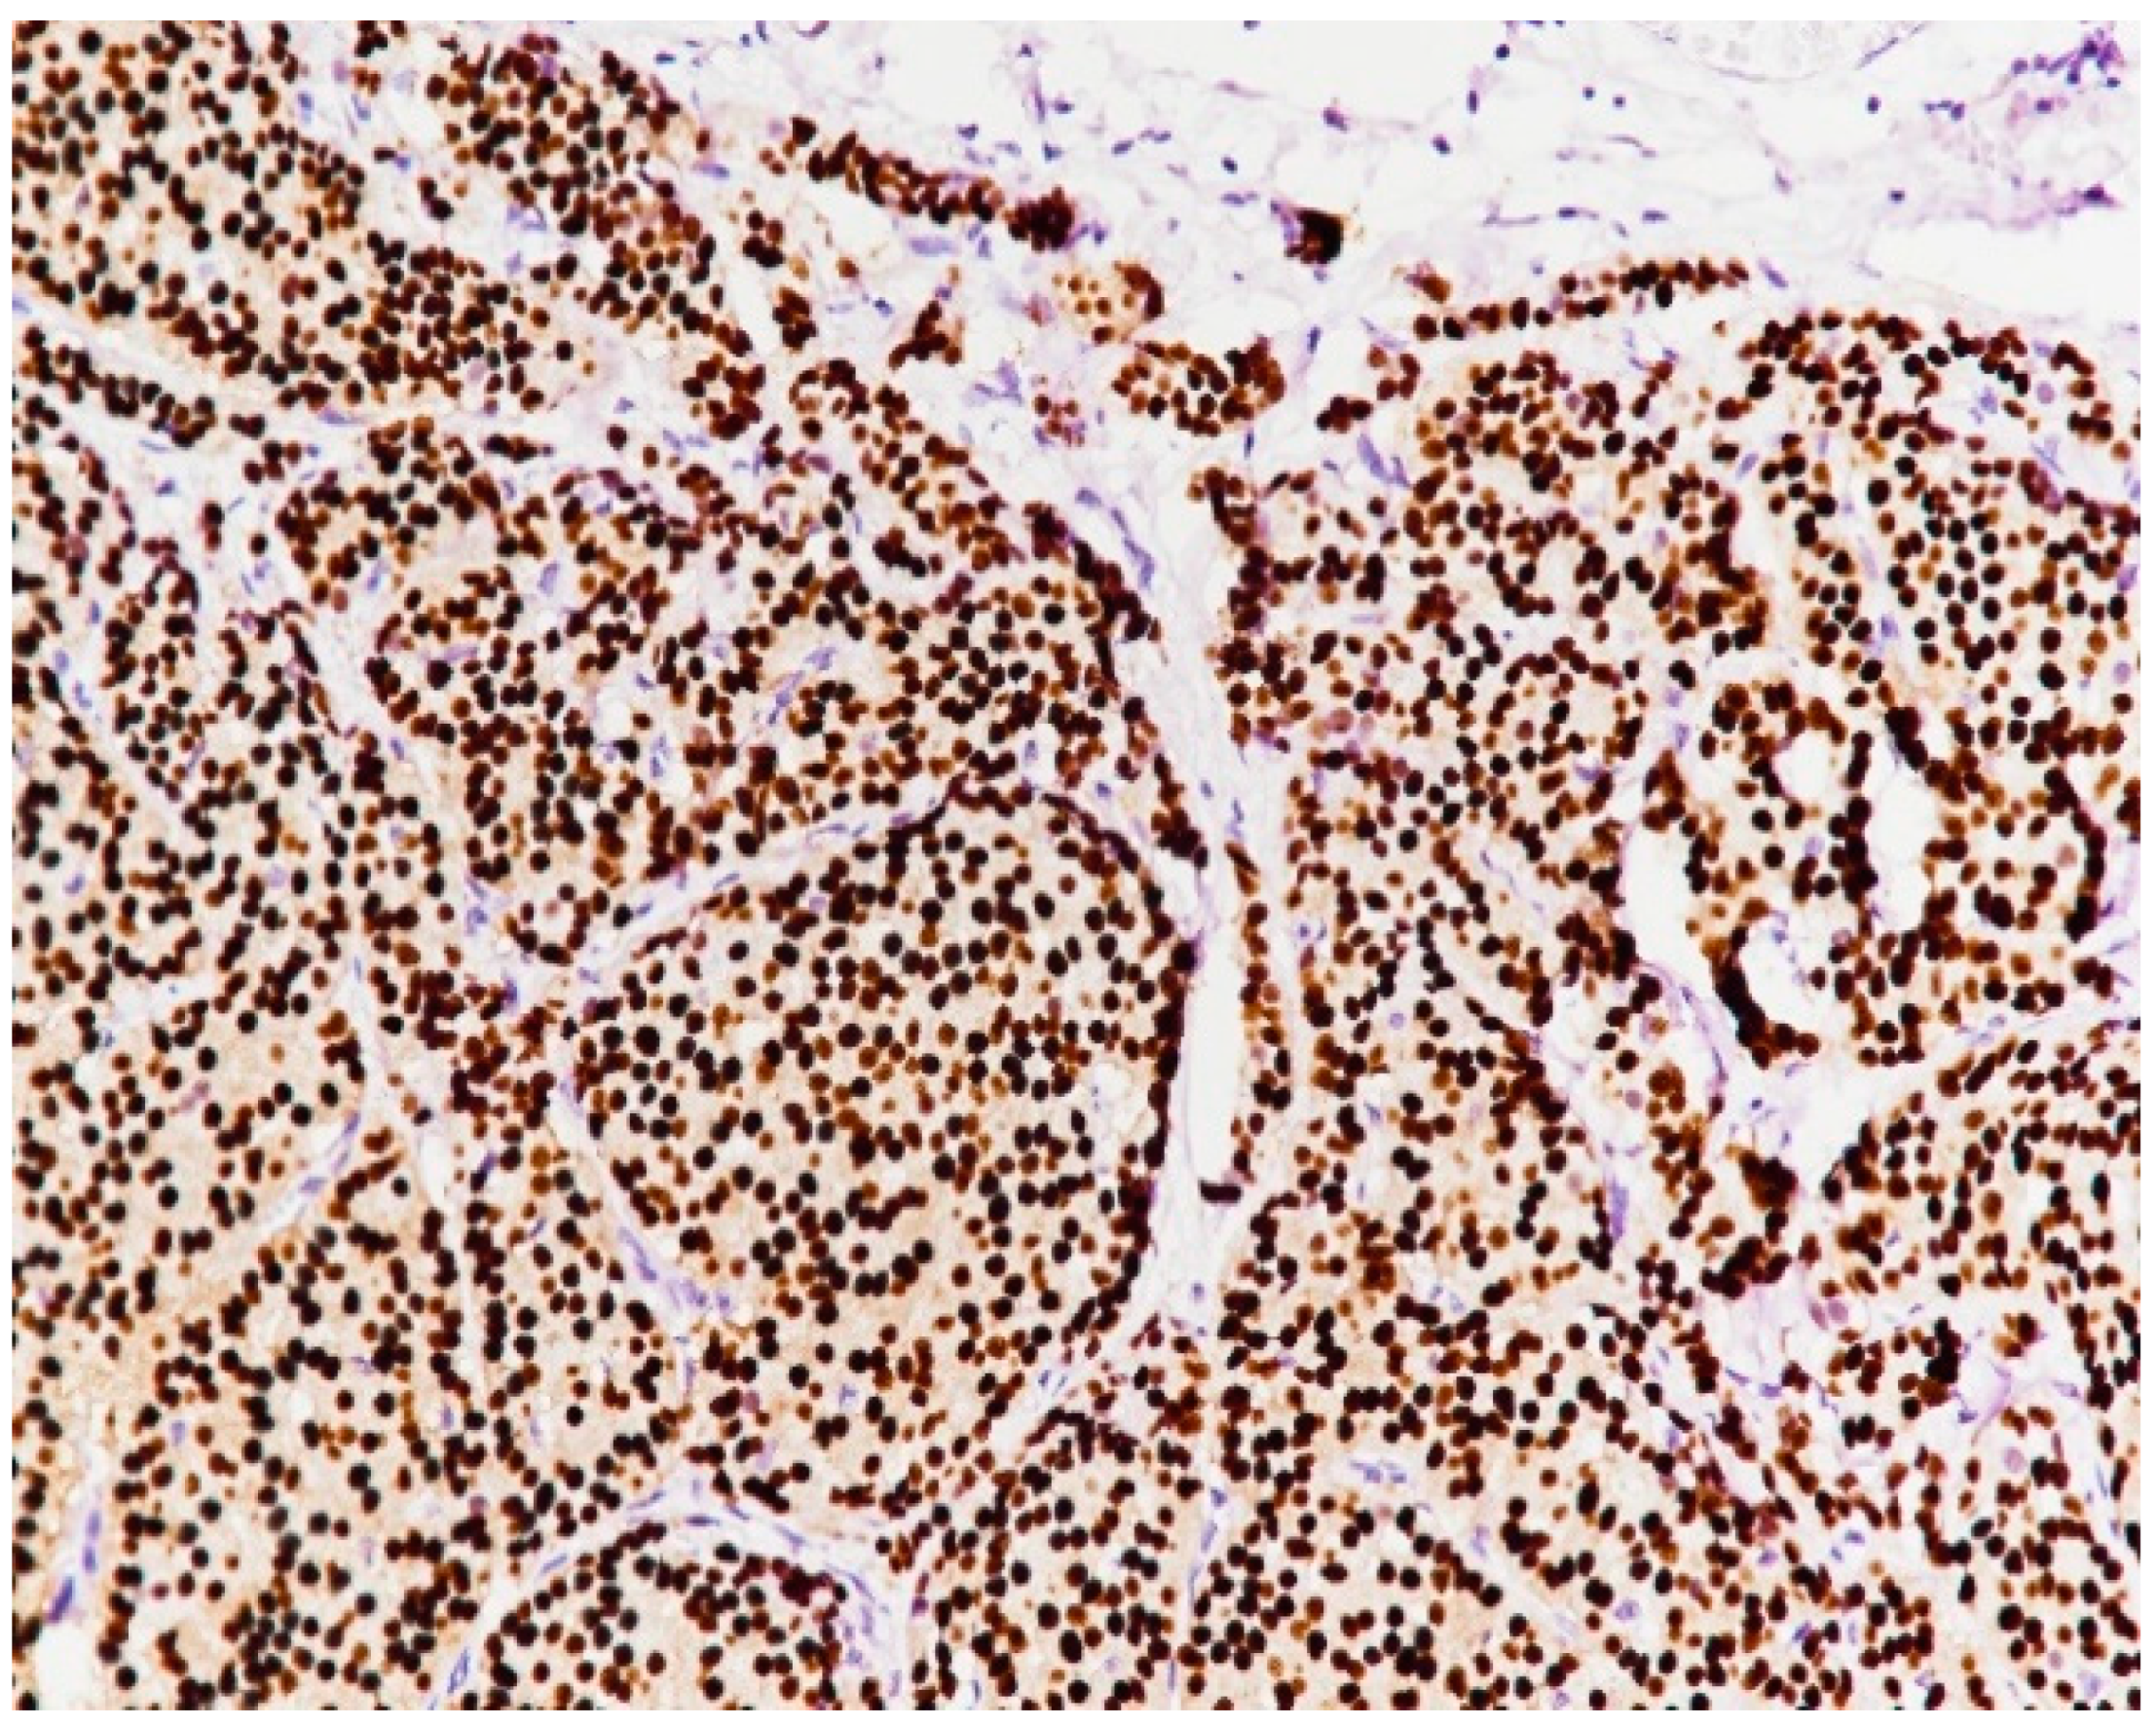

2. Case Presentation

3. Discussion